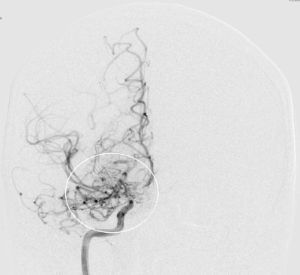

Angiografie einer Moymoya

Auf dem Bild mit einer Gefäßdarstellung “Angiographie” kann man die dünnen Kollateralen (Wolken-ähnliches Bild) um die Gefäßengstelle am Ende der inneren Halsschlagader erkennen.

Die konventionelle cerebrale Angiographie ist die wichtigste Untersuchung zur Diagnosestellung der Moyamoya Krankheit. Diese Untersuchung ist zu vergleichen mit einer Herzkatheteruntersuchung, eben nur mit Darstellung der Hirnarterien. Bei Moyamoya-Patientinnen und Patienten werden, im Gegensatz zu Routineuntersuchungen bei anderen cerebralen Erkrankungen, selektiv die vordere und hintere Zirkulation des Gehirns dargestellt, sowie auch die Versorgung der extrakranialen Gefäße. Diese umfassende Darstellung ist besonders wichtig, um die vollständige Ausdehnung der Erkrankung zu erfassen und alle möglicherweise veränderten Blutflüsse im Gehirn zu verstehen. Je nach Befund werden die Engstellen der Hirnarterien, sowie auch mögliche begleitende Veränderungen selektiv hochauflösend dreidimensional dargestellt. Es ist wichtig zu erwähnen, dass die Moyamoya Krankheit nicht über eine Katheterintervention (Ballonaufweitung der Engstelle) behandelt werden kann und darf. Dies haben mehrere Studien gezeigt.

Angiographie beidseitige Moyamoya Krankheit

Konventionelle Angiographie eines Patienten mit beidseitiger Moyamoya Krankheit (links). 3-dimensionale Darstellung eines Aneurysmas einer jahrelang stark beanspruchten Spontan-Kollaterale (rechts).

Angiographie zur Darstellung der zusätzlichen Blutversorgung des Gehirns

1 Jahr postoperativ: Angiographie zur Darstellung der zusätzlichen Blutversorgung des Gehirns über den Bypass (linke Seite) in Ergänzung zu der unzureichenden Versorgung über die innere Halsschlagader (rechte Seite).